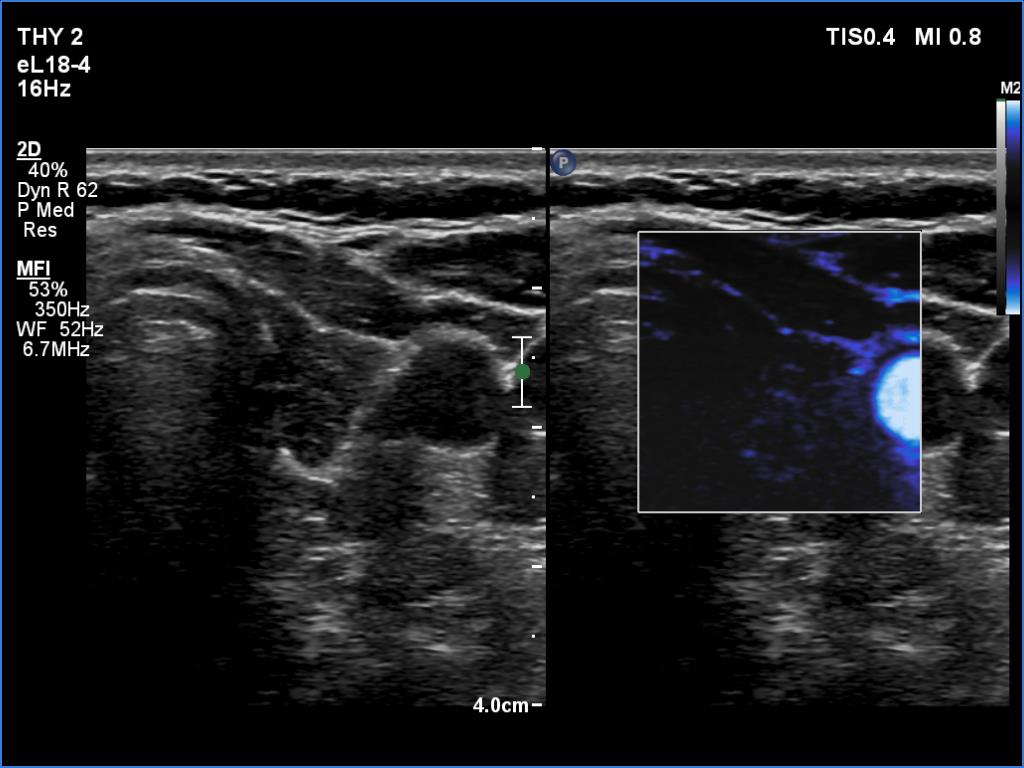

Left lobe, transverse view, microflow imaging. The vascularity is very scanty.